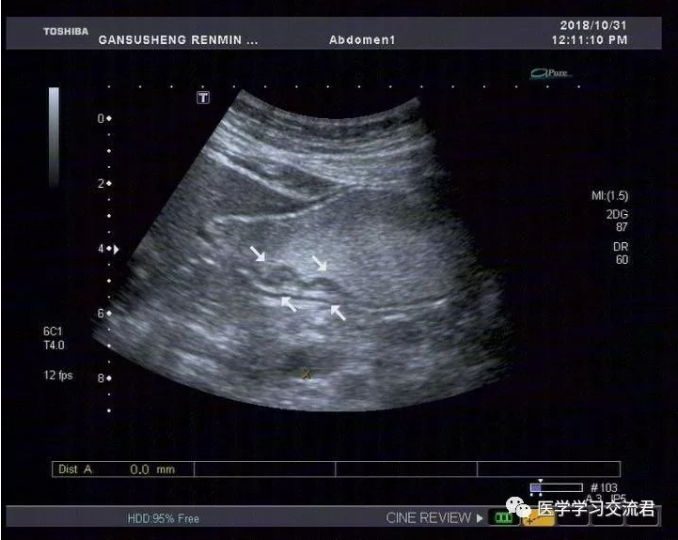

嘱患者饮胃肠造影剂1000ml后扫查:胃贲门及幽门造影剂通过顺畅,胃窦后壁胃壁局限性不均匀增厚,累计长度约19.8mm,最厚处7.4mm,粘膜面连续性中断,可见6mm粘膜凹陷,其内见强回声斑附着,粘膜下层连续完整,局部胃蠕动僵硬,造影剂通过顺畅,余胃壁各层次清楚,粘膜光滑连续,蠕动良好,未见明显肿块及溃疡灶,十二指肠球部充盈好,内未见异常回声。

诊断:胃窦后壁胃壁局限性不均匀增厚并溃疡形成

(早期胃MT?或其他?)

根据2010年国际抗癌联盟/美国癌症联合委员会ICC/AJCC)TNM 分期标准并结合正常胃壁声像图表现得出超声下T分期标准:T1—病变局限于胃壁前三层(强—弱—强)回声线,未突破第三层强回声线;T2—病变侵及胃壁第四层弱回声线,但尚未突破该层结构;T3—病变侵及第五层强回声线但尚未中断;T4—病变突破第五层强回声线,甚至侵犯胃周组织。早期胃癌超声造影图像主要表现为:病变处胃壁局限性不均匀性增厚,回声减低,稍隆起于胃腔内或呈浅凹陷,局部胃壁黏膜层和黏膜肌层破坏、层次不清,与周围正常黏膜界限不清,黏膜表面不光滑或粗糙不平,有时可出现浅而大的黏膜凹陷,深可达黏膜下层,凹陷周缘胃壁水肿增厚,凹陷底部较宽而平,表面常附有不规则强回声斑,病变处胃壁蠕动减弱,局部有僵硬感。

该病例病灶浸润深度仅局限于胃壁的黏膜层或黏膜肌层,黏膜下层连续完整,与良性溃疡性病变在影像学诊断上有一定交叉重叠性,故需仔细甄别且须结合胃镜活检后的最终病理结果。